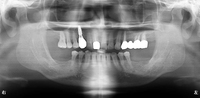

保存が難しい歯をすべて抜歯し、欠損したところは

・右上の前歯をインプラント

・下の両奥歯を義歯

・左上はブリッジ

のコンビネーションで修復しました。

術後

下の奥歯は義歯を使用して頂いています。(写真には写っていません)

治療期間:約2年